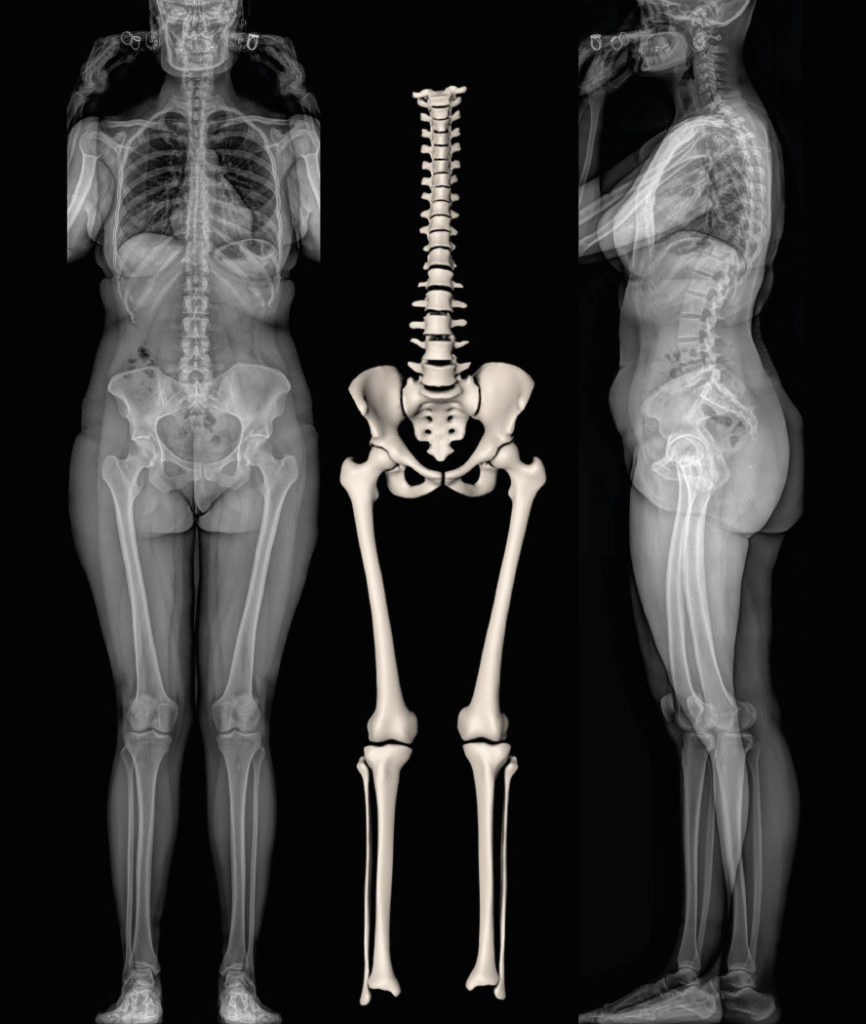

Full Female Body X-Ray With Skeleton 3D model rigged | CGTrader

Full Female Body X-Ray With Skeleton 3D model rigged | CGTrader

Full Female Body X-Ray With Skeleton 3D model rigged | CGTrader